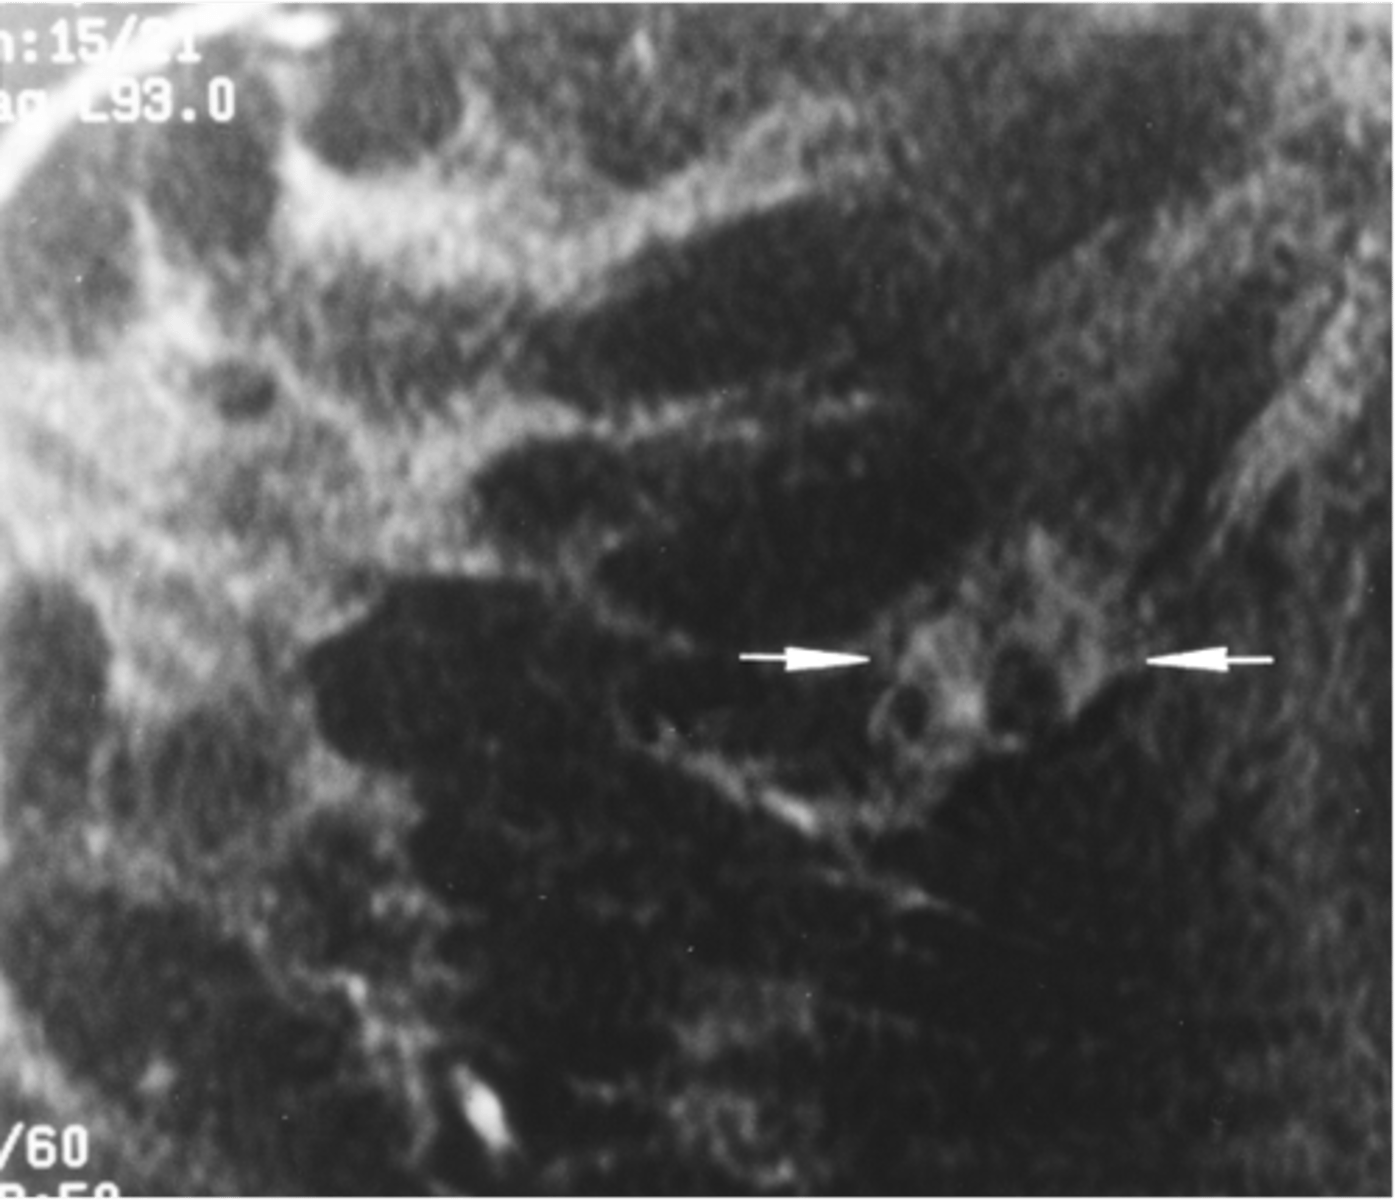

breast cancer

30-90 yo (mostly > 50)

Usually single mass

Irregular or stellate shape

Firm, hard consistency

Not well-demarcated

May be fixed

Usually nontender

May see skin changes or nipple retraction